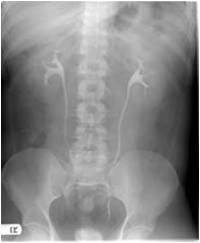

Radiograph #1

Identify: Minor calyx, major calyx, renal pelvis, ureter, left kidney, right kidney, ala sacrum.